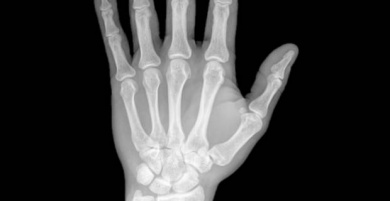

Geralmente, os primeiros sintomas dessa doença são dores nas extremidades e muita dificuldade para movê-las.

A artrite reumatoide provoca inflamação nas articulações e nos tecidos, por essa razão, o movimento natural das rótulas é dificultado. Trata-se de uma doença doença autoimune, o que quer dizer que é o próprio organismo que ataca ele mesmo por um erro.

Quase todas as pessoas que têm essa doença sofrem dores intensas nas articulações, essas dores se tornam muito mais fortes durante as madrugadas; também costumam sentir um intenso calor, enrijecimento e deformação das articulações.

Além disso, sentem adormecimento das mãos e pés, acompanhado de outras doenças como a síndrome do olho seco.